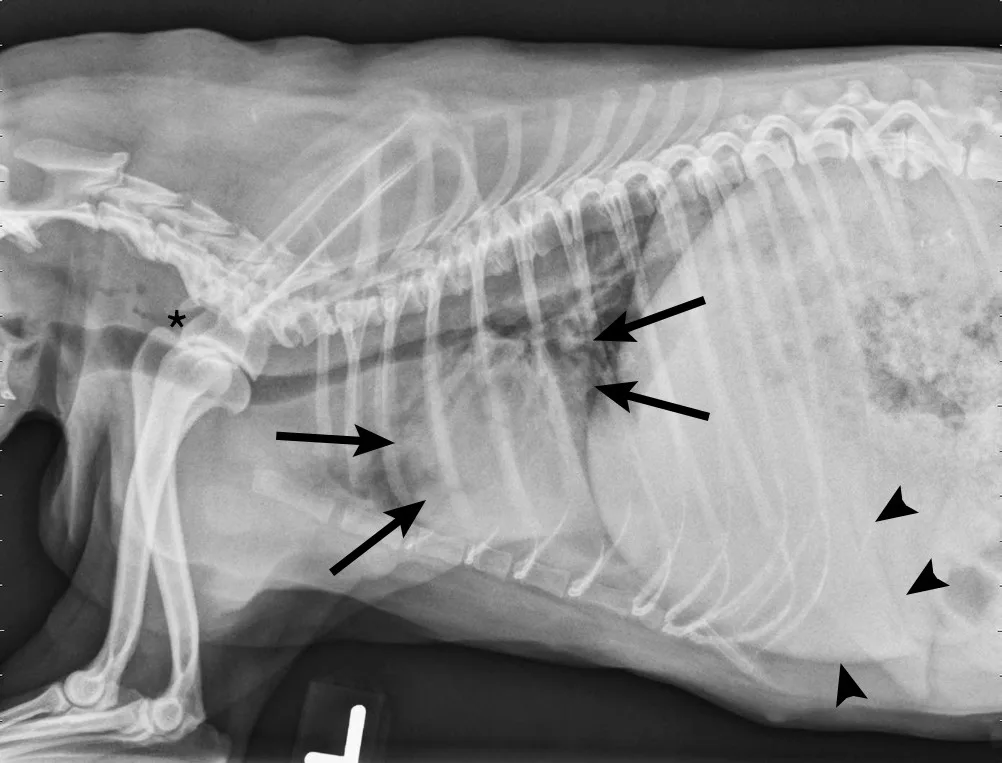

On examination, the dog was panting with expiratory effort and crackles auscultated diffusely. She exhibited an occasional goose-honking cough and retch. Her body temperature was normal. Radiography (Figures 1 and 2), fluoroscopy (Figure 3), and bronchoscopy (Figures 4 and 5) were performed.

FIGURE 1

Left lateral radiograph showing dynamic collapse of the intrathoracic trachea from the level of the thoracic inlet to the mainstem bronchi. A small amount of esophageal gas is observed (asterisk), and the lungs are hypoinflated, which is likely secondary to increased respiratory effort. Mild, generalized cardiomegaly and hepatomegaly are also evident in the thorax (arrows) and abdomen (arrowheads), respectively.